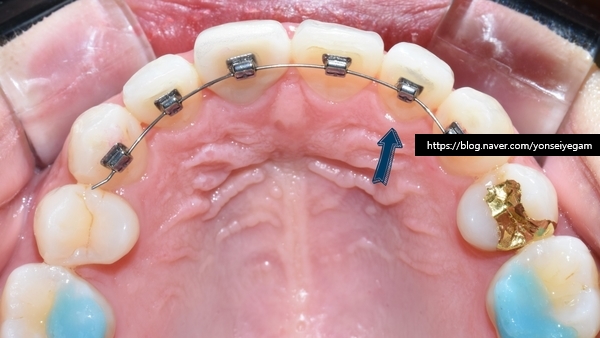

보이지 않게 설측에 붙이는 티끌교정으로 진행하였습니다.

치아안쪽에 장치를 부착하기 때문에 겉에서는 보이지 않습니다.

요렇게 티끌장치를 붙였고, 2주만에 이렇게 변화하셨습니다.

치아의 배열이 달라진게 느껴지시나요?

조금더 넣고 싶다고 하셔서 더 진행하고

요렇게 마무리 되었습니다.

물론 안쪽에는 다시 틀어지지 않기 위해 유지장치 부착되어있습니다.